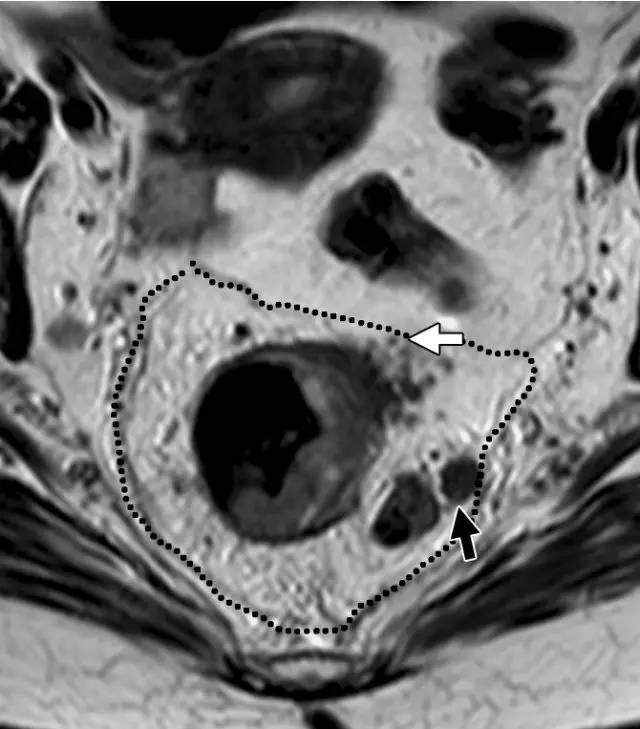

图 32 轴向 T2 加权图像报告 CRM 的距离。T3c 肿瘤,靠近腹膜的 EMVI(白色箭头)和不规则信号强度淋巴结的 T3c 肿瘤,通过毗邻直肠系膜筋膜的淋巴结包膜(黑色箭头)肿瘤扩展(预测 CRM = 0 mm)。